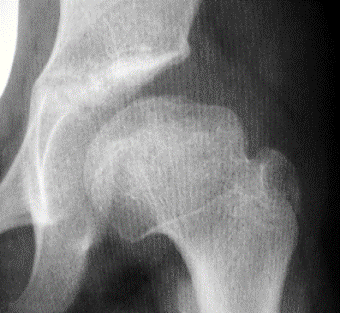

LEGG PERTHES

Enfermedad de Legg Perthes

necrosis avascular y aséptica